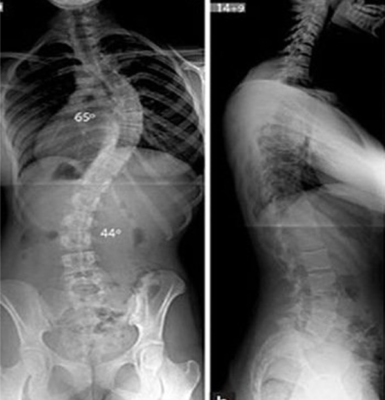

Ngoài ra, cong vẹo cột sống còn được phân loại theo vị trí (cổ, ngực, thắt lưng) và độ cong (nhẹ: <20°, trung bình: 20-40°, nặng: >40°).

- Chụp X-quang: Giúp xác định chính xác độ cong và vị trí cong vẹo.

- Áp dụng cho trường hợp nặng (độ cong >45-50°)